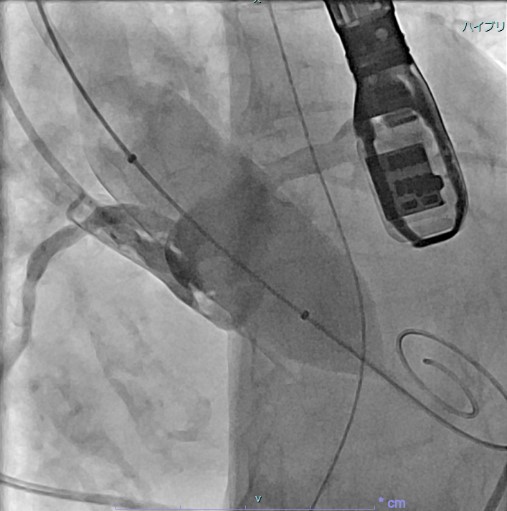

両心室ペーシング機能付き植込型除細動器移植術

(血管撮影)

両心室ペーシング機能付き植込型除細動器移植術

(X線撮影)

治療では、狭窄した冠動脈を風船で広げ、ステントと呼ばれる金属でできた網目状のデバイスを留置する冠動脈拡張術(PCI)や、不整脈の原因となる電気回路の遮断のために心筋を高周波電流で焼却するアブレーション治療、ペースメーカーや植込み型除細動器などのデバイス埋め込み術などがあります。

治療では、狭窄した冠動脈を風船で広げ、ステントと呼ばれる金属でできた網目状のデバイスを留置する冠動脈拡張術(PCI)や、不整脈の原因となる電気回路の遮断のために心筋を高周波電流で焼却するアブレーション治療、ペースメーカーや植込み型除細動器などのデバイス埋め込み術などがあります。